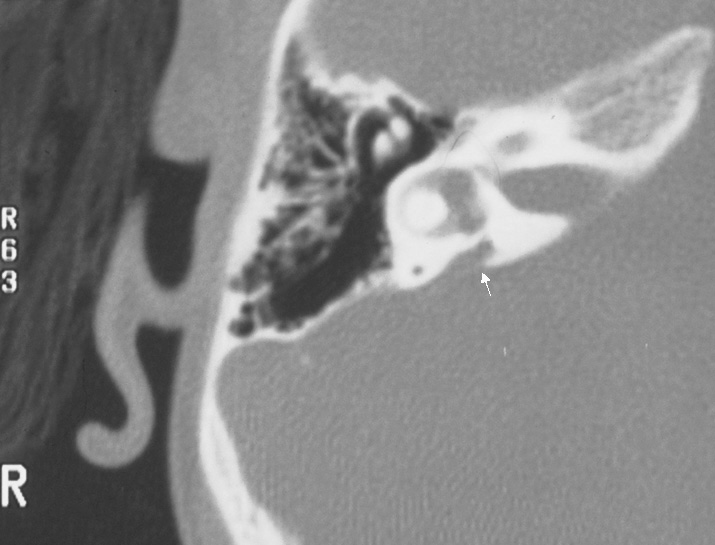

Diagnosis is made by high resolution CT of the temporal bones.